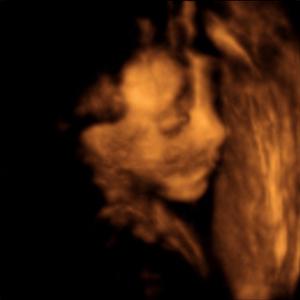

Hallo ihr lieben wer hat von euch schon mal ein 3D film machen lassen von dem klein würmchen im bauch

nur leider wollte der kleine sein gesicht nicht zeigen konnte machen was ich wollte seine hand war da vor

Ich. In der 24. SSW. Man hat gesehen wie er mit der Gebärmutterwand "kuschelt". Zwischen die Beine hat er sich nicht gucken lassen. LG Mausi mit Hendrik heute 9 Monate alt.

Ich hab bei meinem ersten Sohn ein Video gemacht... er sieht sichs auch gerne an ;) hab esehn wie er fruchtwassergetruunken hat an seinem daumen genuckelt usw mein video wurde in der 28 ssw gemacht. lg